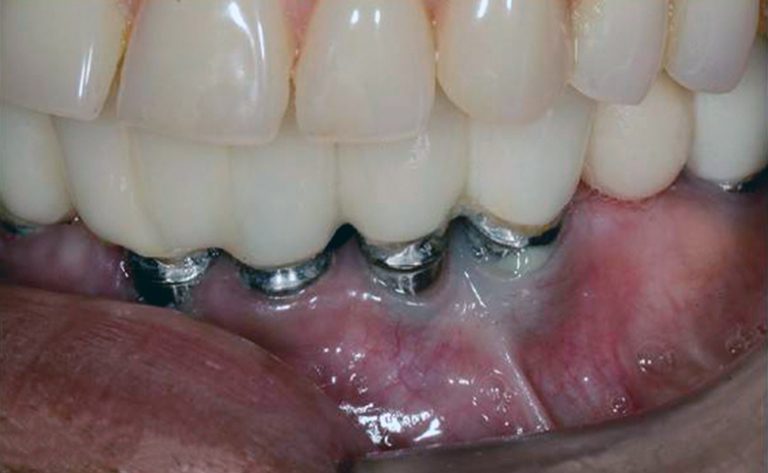

Это воспалительный процесс деструктивного характера, который затрагивает мягкие и твердые ткани зуба, окружающие имплантат. Со временем начинает разрушаться костная ткань, что приводит к расшатыванию титанового корня. Причина развития патологии связана с бактериями, которые проникают в десну и накапливаются на поверхности имплантата.

- Оголение имплантата

Через несколько лет после установки имплантата происходит небольшая убыль кости. Это естественный процесс, который считается нормой. Несмотря на то, что производители стремятся свести подобное явление к минимуму, улучшая конструктивные особенности имплантатов, полностью избежать резорбции костной ткани пока невозможно. В результате оголяется шейка имплантата. Если у пациента плохая домашняя гигиена, то на оголенном участке конструкции начинают скапливаться и размножаться бактерии, что приводит к развитию периимплантита, а затем – к отторжению титанового корня.